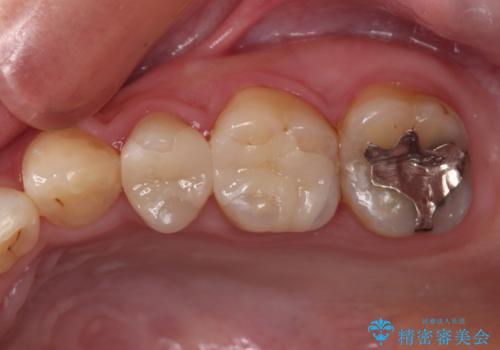

まだ銀歯が残っていますが、大きく目立つ銀歯をセラミックに置き換えることができ、人前で口を開けることを気にしなくなりました。

補綴治療中の後戻り対策をしっかりと行ったことで、歯列全体をきれいに整えることができました。